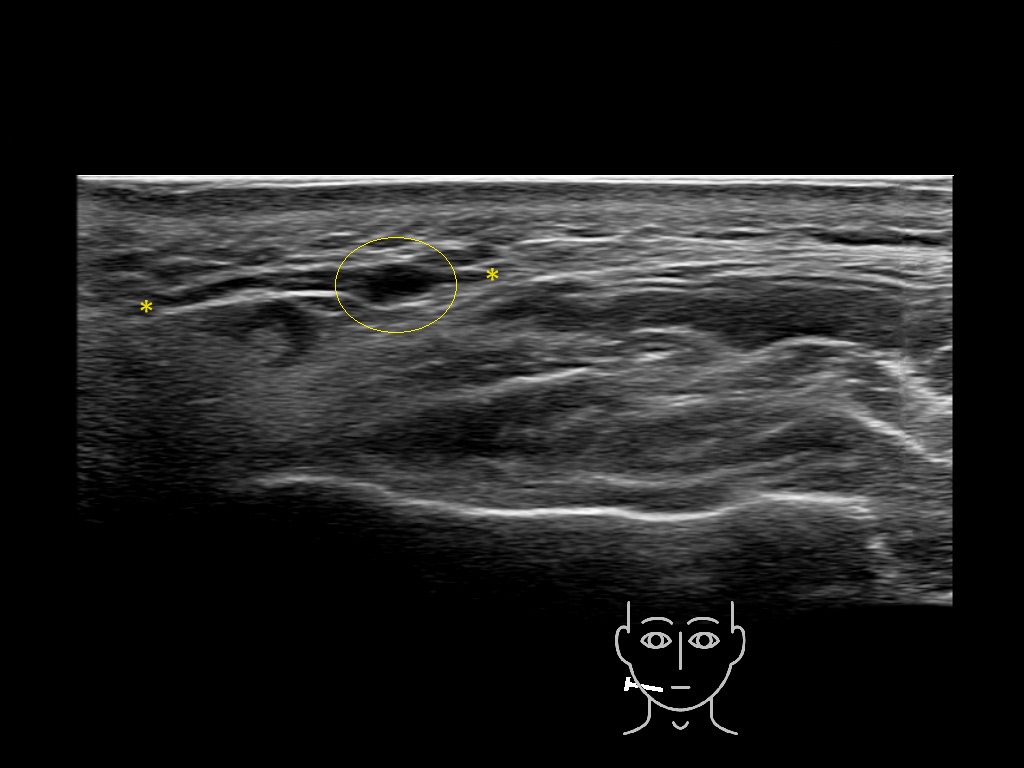

Filler deposits may end up unintentionally in the SMAS or fascial layers of the skin. Very often this will not lead to adverse events, however, adverse events ( nodules, migration / redistribution impaired muscle movement and smiling and malar edema) are are often related to filler ending up in the SMAS or fascia.

Study the first image to recognize the different layers. If you are sure about the layers, swipe to the second image to view the answer (if applicable).